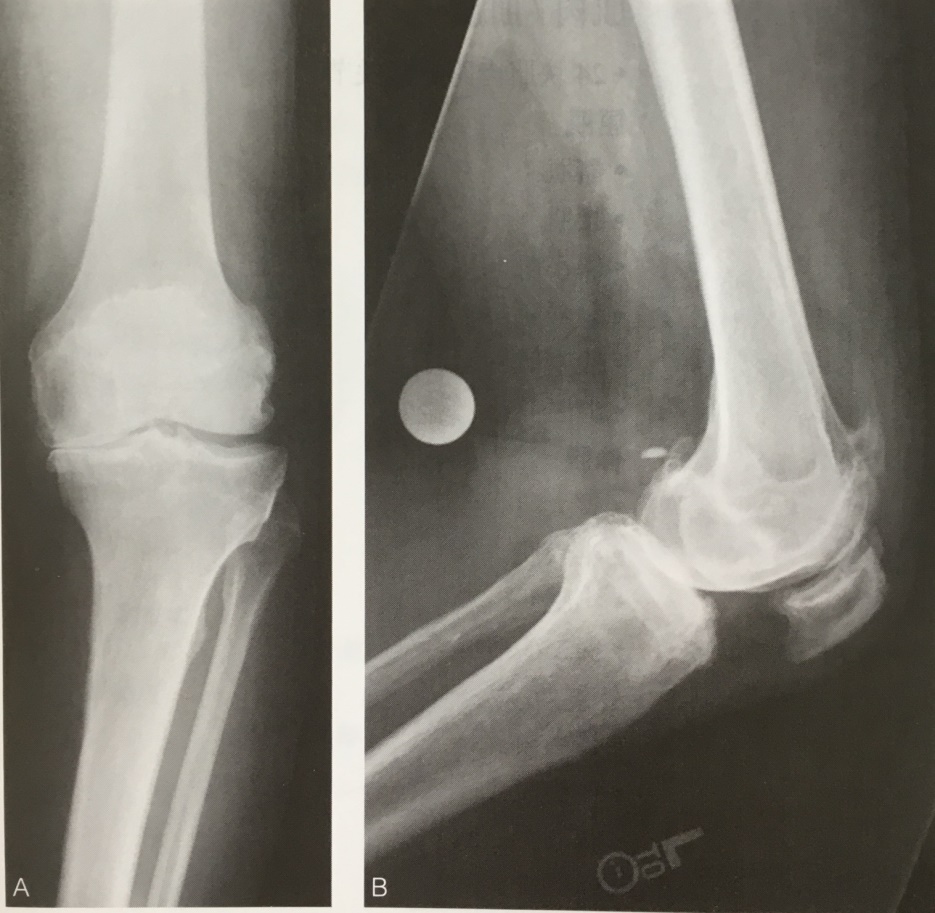

X光片

从上图膝关节的正侧位片我们可以发现:左膝内侧关节间隙几乎消失了,这提示软骨肯定是磨损了。另外,我们可以发现很多向鸟嘴一样的刺,这是所谓的骨质增生。其实,这个骨质增生就是我们老百姓经常说的骨刺,临床上叫骨赘。

骨刺=骨质增生=骨赘